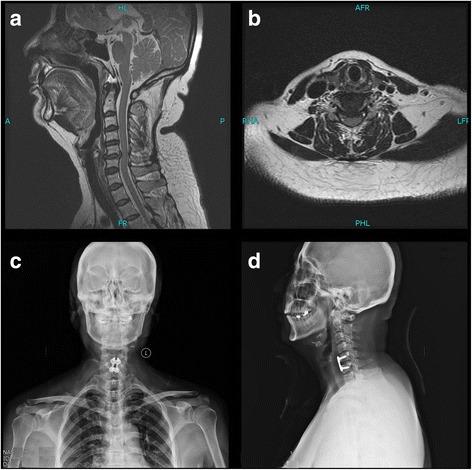

颈椎病患者前路颈椎间盘切除融合术与人工椎间盘置换术对比——一项8年随访研究

ACDF vs TDR for patients with cervical spondylosis - an 8 year follow up study.

前路颈椎间盘切除融合术(ACDF)一直被视为治疗单节段颈椎间盘突出症的金标准。然而,由于局部生物力学改变,它可能导致相邻节段退变。人工颈椎间盘置换术(TDR)已应用十多年,效果令人满意,但对于TDR是否比ACDF更安全、更有效尚无共识。本研究旨在比较TDR和ACDF治疗单节段颈椎间盘突出症患者的有效性和安全性。

方法

本研究纳入了在我们中心连续接受TDR或ACDF手术的145例患者。比较手术时间、术中失血量、视觉模拟评分法(VAS)上肢和颈部疼痛评分、活动度(ROM)、颈椎功能障碍指数(ODI)、简明健康状况调查量表(SF36)以及患者满意度,这些指标在手术前、手术后以及术后1、3、5、8年的随访期间进行评估。